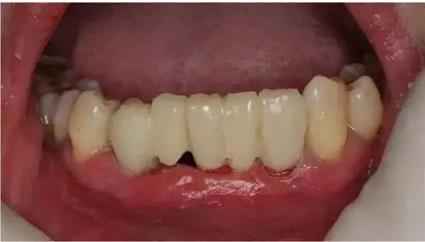

臨時(shí)冠就位,即刻修復(fù),無咬合接觸